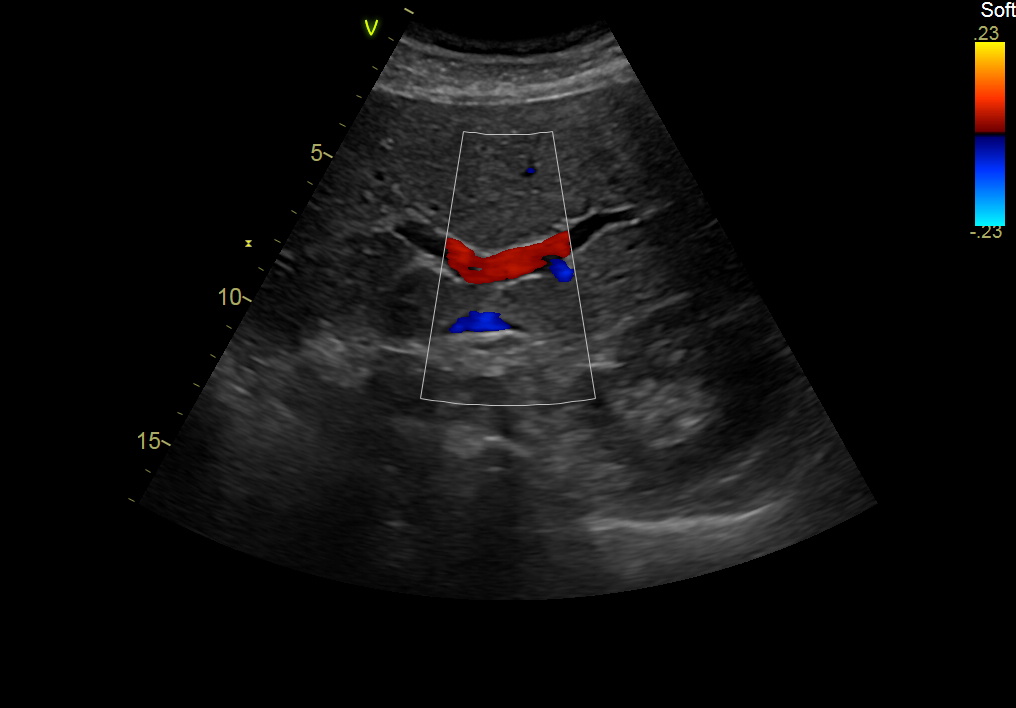

GE C1-6-D Abdominal Convex Refurbished

GE Convex C1-6-D Abdominal

Intended use

Abdominal and Women’s Health

Frequency Range

6 – 1 MHz

GE C1-6-D Abdominal Convex

Frequency Range: 6 – 1 MHz

GE C1-6-D Abdominal Convex for Abdominal and Women’s Health